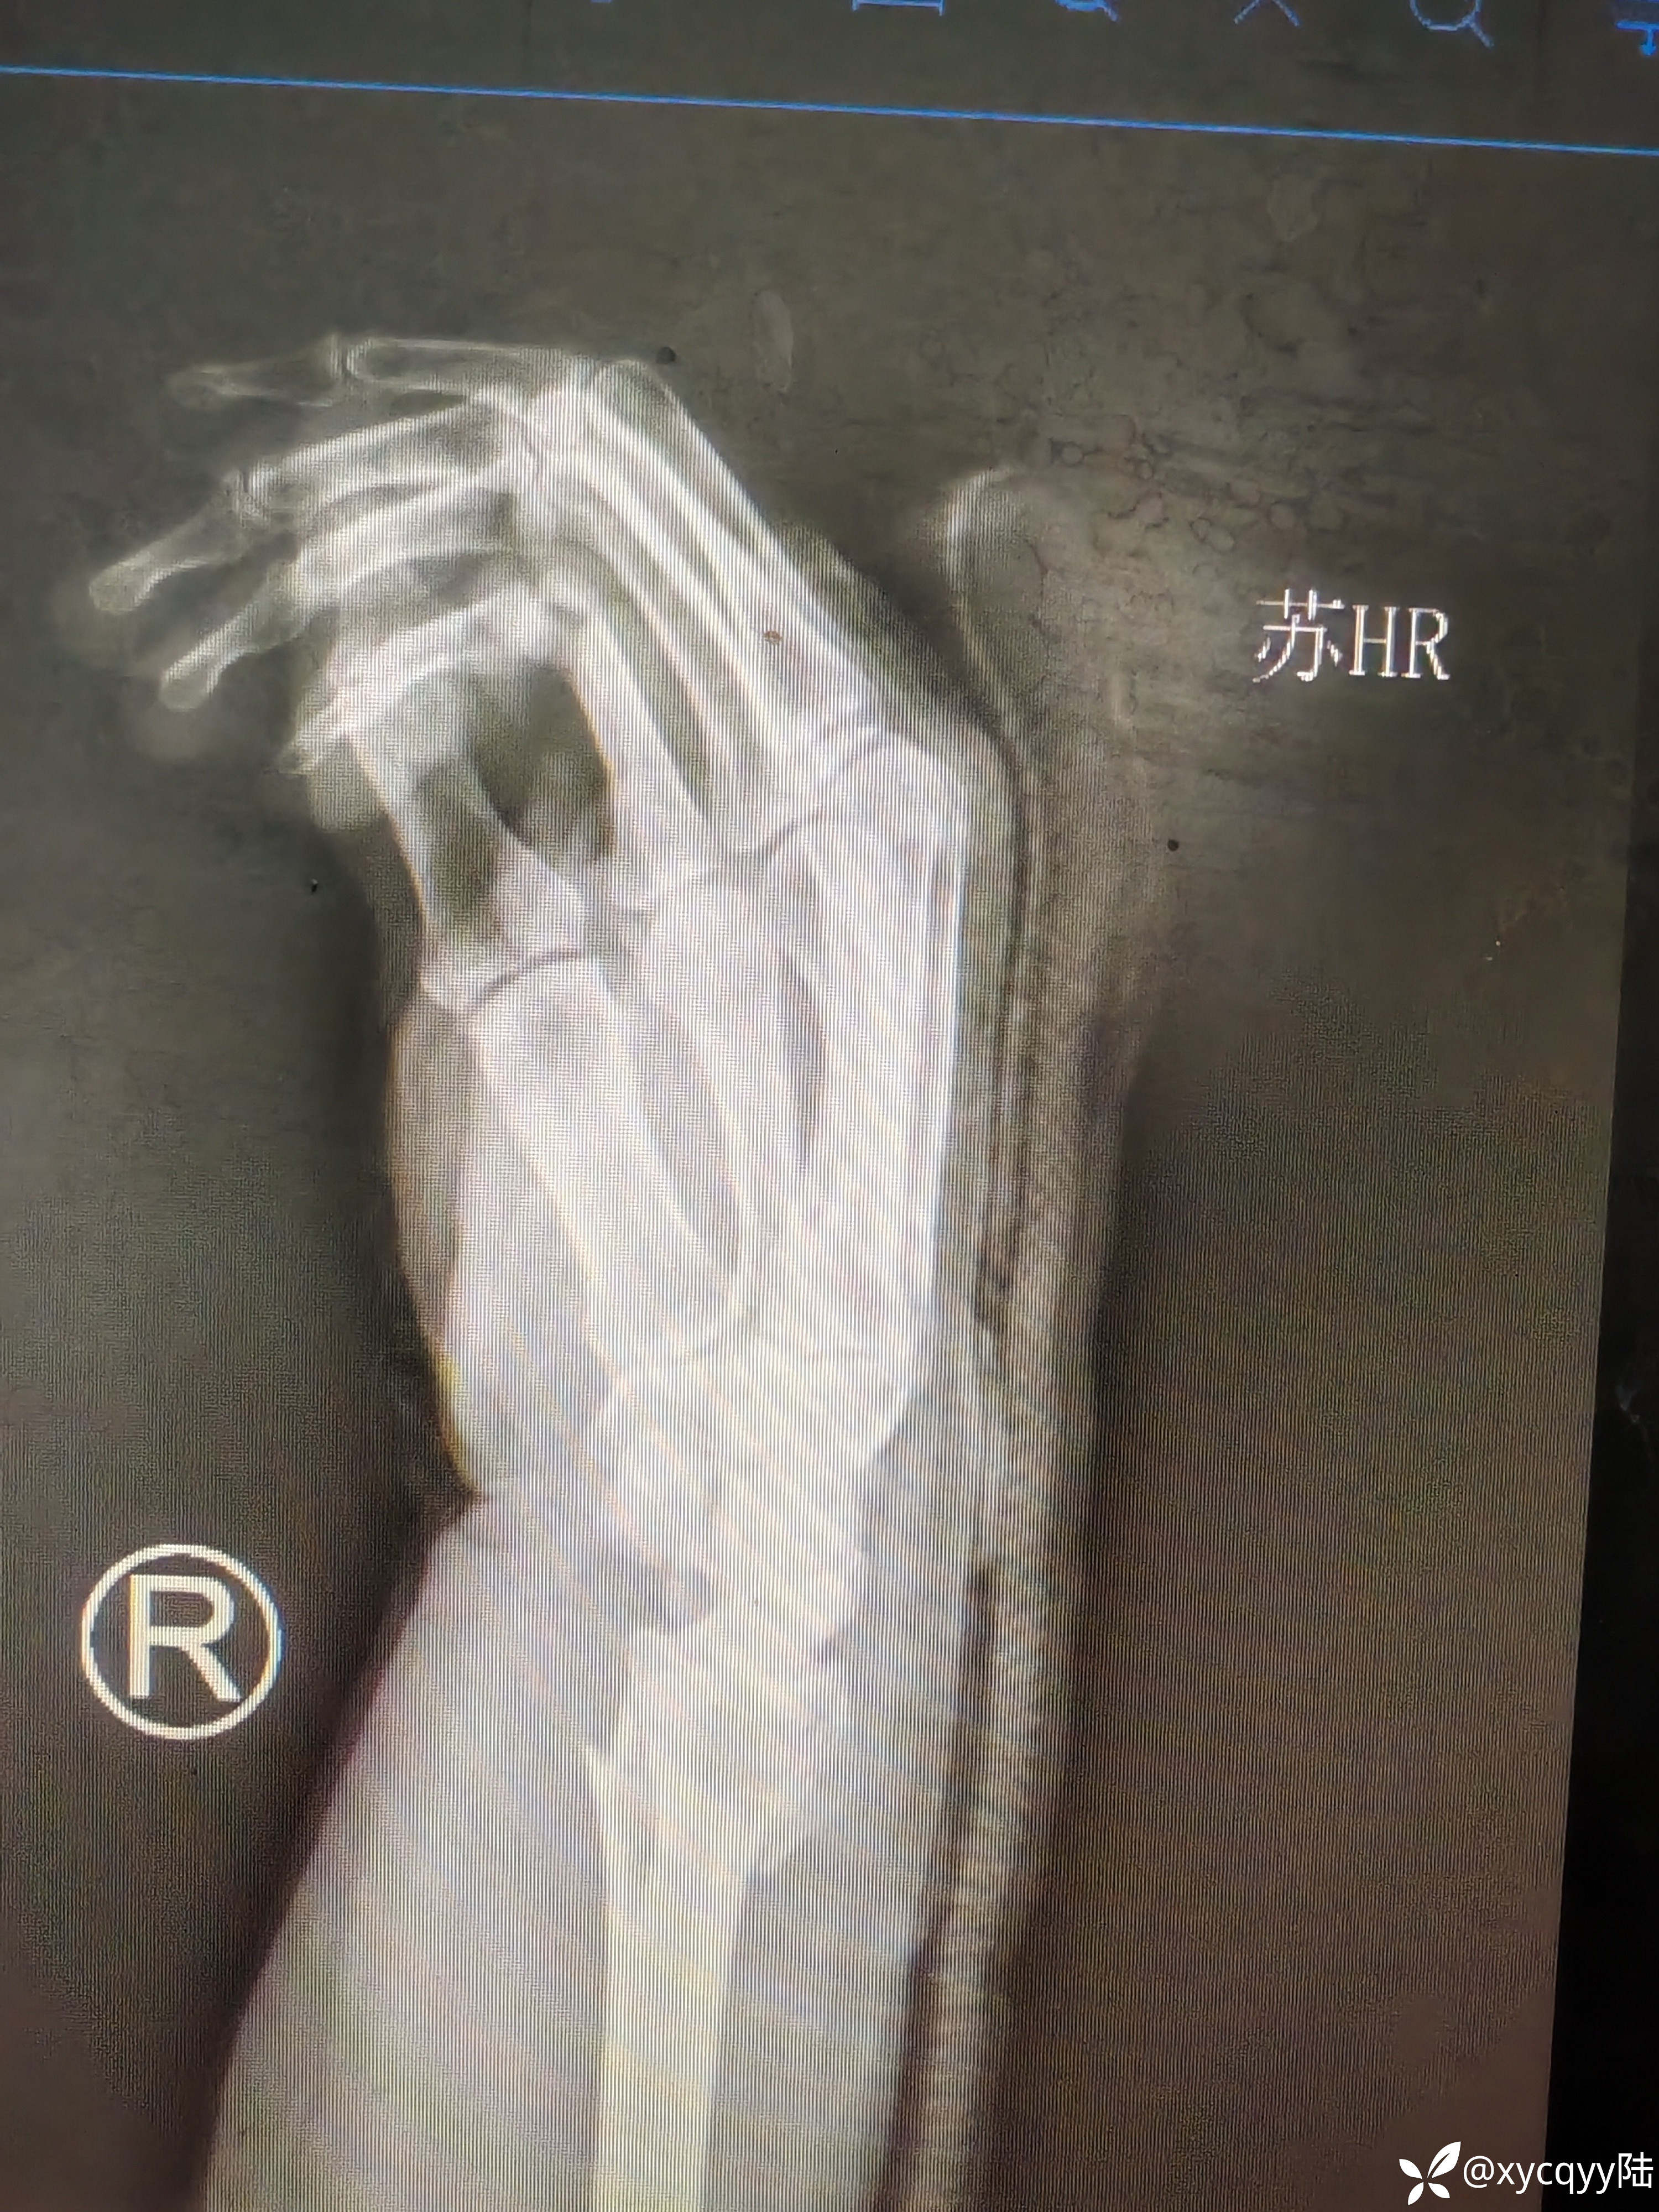

女,60岁,外伤桡骨远端骨折尺骨茎突骨折复位后效果